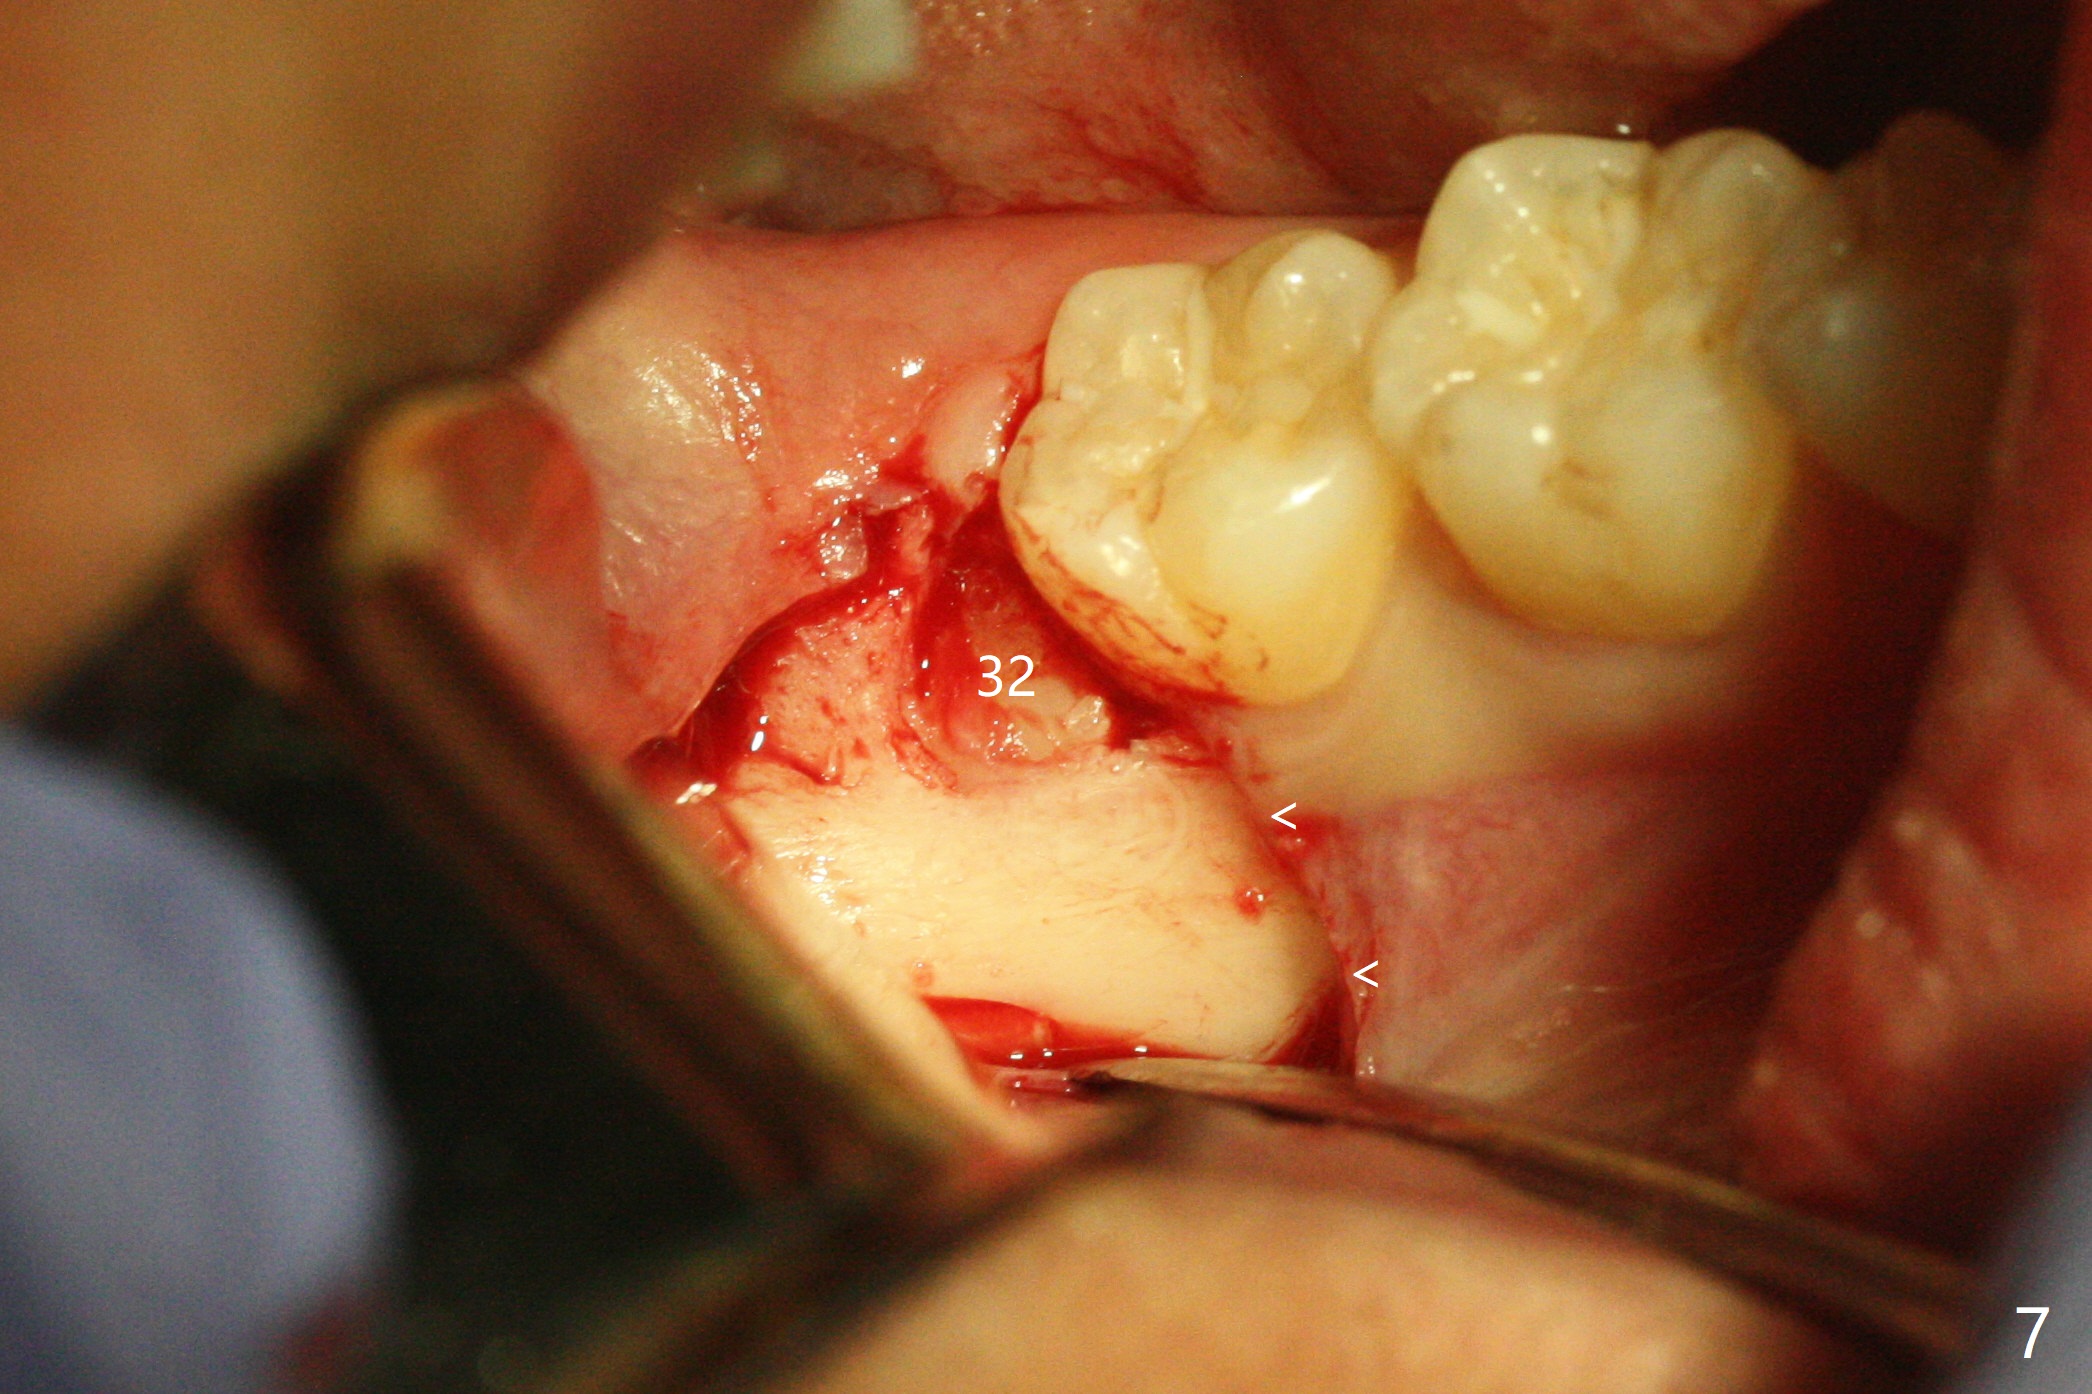

A 25-year-old woman, under our care for the last 11 years (Fig.1-6), returns for #1 and 32 extraction (1 year after #16 and 17 extraction (Osteogen plug)). Preop PA shows that a portion of the lower impacted tooth may be located buccal to the tooth #31 (Fig.4 black dashed line). An accessory incision is moved from distobuccal to midbuccal (Fig.7 arrowheads) to reduce postop loss of bone graft (Fig.8 B) from the incision. In fact the incision should be further moved to mesiobuccal (Fig.9 red line) if buccal impaction is suspected (curved black line). The buccal impaction of #32 of her father is more severe.